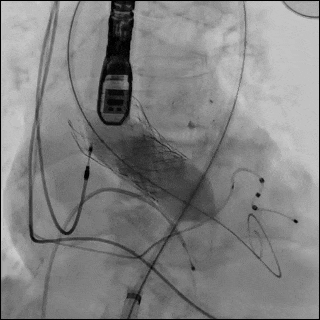

(左图)一名84岁女性因既往植入的 Evolut R 瓣膜出现严重瓣环钙化,接受23 mm S3UR瓣膜行 redo-TAVR。该患者最初因钙化的1型双叶主动脉瓣而植入 Evolut R 瓣膜。(中图)在瓣膜释放过程中,球囊近端发生破裂,远端球囊形成类似“伞状”结构。破裂部位对应严重的瓣上瓣叶钙化区域。(右图)呈伞状的远端破裂球囊无法通过14F鞘管回撤。因此整体取出输送系统及鞘管,将鞘管升级至16F,完成后扩张,并置入覆膜支架修复受损的髂股动脉。

左前斜造影以获取最佳的瓣架对齐视角,可见 node 4 与 node 5 之间存在严重钙化,对应原Evolut R 瓣膜的瓣环上瓣叶区域。(图4,视频3)

在node4、node5之间可见严重钙化(白色箭头),对应原 Evolut R 瓣膜的瓣上小叶。

采用21 mm TRUE 球囊行主动脉瓣预扩。在钙化的 Evolut R 瓣叶水平可见明显的“球囊腰征”(图6,视频6),提示严重瓣叶钙化导致扩张受阻。

(A)使用 21 mm TRUE balloon 行主动脉瓣预扩张。于钙化的 Evolut R valve 瓣叶水平可见明显“球囊腰征”(白色箭头),提示充盈过程中存在显著阻力。(B)植入 23 mm SAPIEN 3 Ultra RESILIA valve(S3UR)过程中发生球囊破裂。球囊远端可见造影剂积聚(白色箭头),形成类似“伞状”外观,提示存在水平撕裂。23 mm 瓣膜未完全释放(白色箭头)。(C)对侧入路行髂动脉造影。可见左侧髂总动脉夹层,但无活动性造影剂外渗(白色箭头)。(D)使用 23 mm TRUE balloon 对未完全扩张的 S3UR 瓣膜进行后扩张。(E)血管内干预后髂动脉造影。将 16F eSheath 回撤至左侧髂外动脉,并于夹层的髂总动脉内植入一枚 8 × 59 mm VBX 覆膜支架(白色双向箭头)。(F)血管内干预后股动脉造影。左侧股总动脉穿刺通路采用 7 × 50 mm Viabahn stent graft 进行封闭(白色双向箭头)。最终造影显示无造影剂外渗,血流通畅。

随后植入23 mm S3UR 瓣膜,其流出端与既往瓣膜支架的 node 4.5对齐。球囊扩张过程中发生破裂,导致瓣膜未完全扩张。球囊远端内造影剂积聚提示存在水平撕裂,形成“伞状”结构,使系统无法通过14F鞘管回撤(图6B,视频7)。

经左股动脉将输送系统及鞘管整体取出,随后更换为16F 鞘管以压迫可能的血管损伤。经对侧髂动脉造影显示左侧髂总动脉夹层,但无活动性造影剂外渗(图6C,视频8)。术中血流动力学始终稳定。

随后采用23 mm TRUE 球囊对未完全扩张的 S3UR 瓣膜行后扩张(图6D,视频9)。后TEE提示瓣膜位置良好,无瓣周漏(PVL)。

将16F鞘管回撤至左髂外动脉水平,并植入一枚8×59mm VBX 覆膜支架用以修复左侧髂总动脉夹层(图6E,视频10和11)。左股动脉穿刺口采用7×50mm Viabahn 覆膜支架进行封闭(图6F,视频12)。最终造影示无造影剂外渗,血流通畅(视频13)。